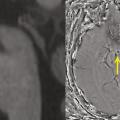

L’extension des DNF dans les hippocampes induit une perte synaptique, puis une mort neuronale, qui finit par engendrer une atrophie hippocampique, visible en imagerie par résonance magnétique (IRM) cérébrale (fig. 1 ). Celle-ci est cependant un signe survenant avec retard par rapport à la clinique. Le défi est de poser un diagnostic de plus en plus précoce de la MA, au stade des prodromes, afin de proposer une prise en charge adaptée.

L’extension des DNF dans les hippocampes induit une perte synaptique, puis une mort neuronale, qui finit par engendrer une atrophie hippocampique, visible en imagerie par résonance magnétique (IRM) cérébrale (